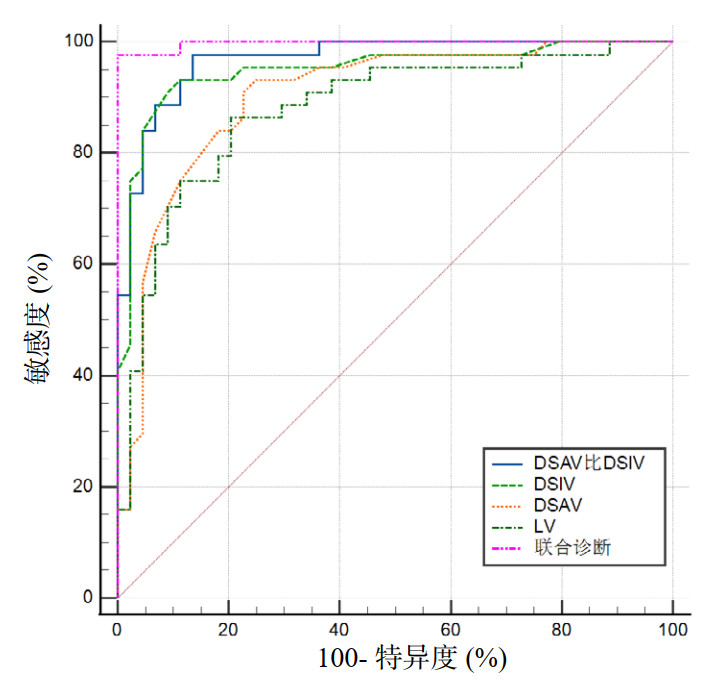

筛选出单因素方差分析后差异具有统计学意义、Spearman相关性分析结果与DL强相关且诊断价值较高的超声指标,纳入二项Logistic回归模型,最终纳入DSAV/DSIV、DSIV、DSAV和LV这四个指标,利用联合诊断Logistic回归预测概率值再次绘制ROC曲线,联合指标的AUC可达到0.997,优于任何单一指标(P < 0.05)。各指标预测DL的ROC曲线参数见表 4及图 3。

| 指标 | AUC(95%CI) | P值 | 截断值 | 敏感度(%) | 特异度(%) |

| DSAV/DSIV | 0.968(0.907~0.994) | < 0.0001 | 0.84 | 97.73 | 86.36 |

| DSIV | 0.950(0.882~0.985) | < 0.0001 | 1.84 cm | 90.91 | 90.91 |

| DSAV | 0.902(0.819~0.955) | < 0.0001 | 0.78 cm | 93.18 | 75.00 |

| LV | 0.878(0.791~0.938) | < 0.0001 | 1.61 cm | 86.36 | 79.55 |

| LE/LV | 0.814(0.716~0.889) | < 0.0001 | 2.62 | 75.00 | 79.55 |

| TMD | 0.719(0.613~0.810) | 0.0001 | 7.23 cm | 59.09 | 77.27 |

| MMT | 0.705(0.598~0.797) | < 0.0001 | Ⅲ级 | 65.91 | 75.00 |

| LE | 0.637(0.527~0.737) | 0.0224 | 4.41 cm | 47.73 | 79.55 |

| 联合指标 | 0.997(0.954~1.00) | < 0.0001 | 0.49 | 97.73 | 100.00 |

| 注:DSAV/DSIV为皮肤到声带前联合的距离/皮肤到真声带下缘的距离,DSIV为皮肤到真声带下缘的距离,DSAV为皮肤到声带前联合的距离,LV为真声带长度,LE/LV为会厌长度/真声带长度,TMD为甲颏间距,MMT为改良Mallampati分级,LE为会厌长度 | |||||

| 图 3 筛选后的气道评估指标及联合指标预测DL的ROC曲线图 Fig 3 ROC curves of the screened airway assessment indicators and their combined index in predicting DL |

本研究结果显示,这些指标可有效预测DL;在单一指标中,DSAV/DSIV和DSIV的预测价值最高,其AUC、敏感度和特异度均优于其他指标。原因可能是:DSAV/DSIV比值能够综合反映会厌和声带的相对位置,而DSIV则直接反映了声带下缘的可视深度,直接影响了喉镜暴露的难易。虽然联合指标的AUC达到了0.997,表现出更高的预测价值,但其测量和计算过程较为复杂,可能限制其在临床中的广泛应用。因此相比之下,DSAV/DSIV和DSIV更适合应用于临床气道评估。另外,TMD、MMT、LE的诊断价值均不高,考虑到其在喉镜暴露时的意义可能不大:TMD仅反映下颌后缩或短颈,应用范围较窄;临床普遍应用的MMT预测能力较低,推测可能与它反映口咽腔体积,却不能评估喉部情况有关;虽然过长的LE会妨碍声门暴露,但本结果中的预测价值并不高,这与Han等[20]通过MRI研究的结果基本相近。本研究中LV、DSIV和DSAV均可反映在喉镜暴露时声门的可视程度,DSAV的测量值、预测价值与前期研究结果相似[5]。此外,本研究引入的DSAV/DSIV和LE/LV等联动指标,能更全面地反映喉镜暴露时的解剖关系,但LE/LV的AUC介于两个单一指标之间,可能与LE的诊断能力较差有关。与传统气道评估方法相比,本研究的超声指标显示出更高的敏感度和特异度。这表明,超声技术在预测DL方面具有显著优势,能够弥补传统方法的不足。这也倡导急诊科及麻醉科医生联合培训、熟练掌握这项技术,为顺利建立急诊患者的气道做好可视化预判与准备、提供及时必要的生命支持。